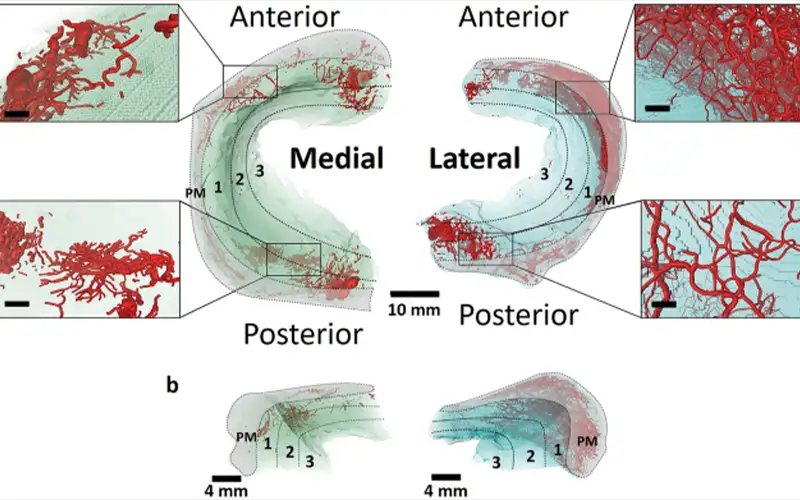

منیسک داخلی زانو ساختاری به شکل حرف C باز دارد و شعاع انحنای آن از منیسک خارجی بیشتر است. منیسک داخلی زانو دارای دو بخش به نام شاخ قدامی و شاخ خلفی است.

شاخ خلفی منیسک داخلی پهنتر از شاخ قدامی بوده و در قسمت جلویی رباط صلیبی خلفی (PCL) به استخوان تیبیا متصل میشود. شاخ قدامی نیز در فاصله حدود ۶ تا ۸ میلیمتر جلوتر از رباط صلیبی قدامی (ACL) به تیبیا اتصال دارد.

قسمت محیطی منیسک داخلی به کپسول داخلی مفصل زانو متصل است و این اتصال از طریق لیگامان کورونری به لبه فوقانی استخوان تیبیا انجام میشود.

منیسک خارجی شکلی نزدیک به C بسته دارد و شعاع آن کمتر از منیسک داخلی است. این منیسک نسبت به نوع داخلی، سطح وسیعتری از بخش فوقانی استخوان تیبیا را میپوشاند.

منیسک خارجی از اطراف به کپسول مفصلی خارجی زانو متصل است. شاخ قدامی آن به ناحیه جلویی برجستگیهای بینکندیلی متصل میشود و شاخ خلفی نیز در قسمت خلفی همین برجستگیها و در جلوی محل اتصال شاخ خلفی منیسک داخلی قرار دارد.